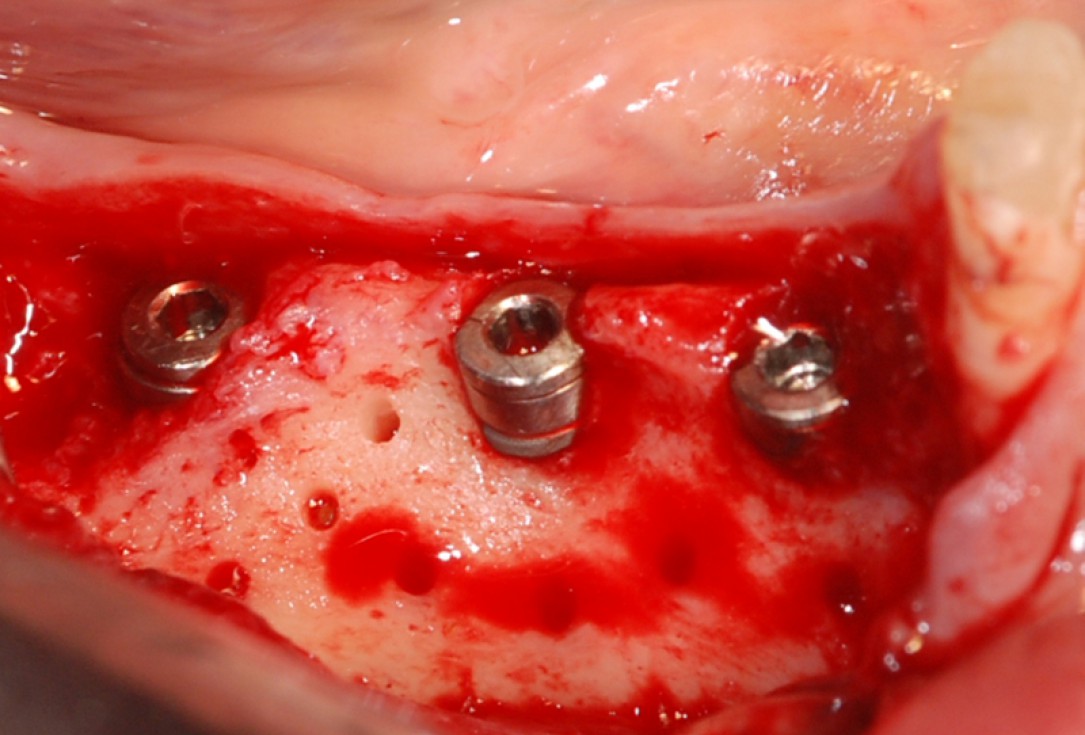

botiss cerabone® & Jason® membrane for horizontal augmentation - Clinical case by Dr. M. Steigmann

Three implants placed in a narrow posterior mandible